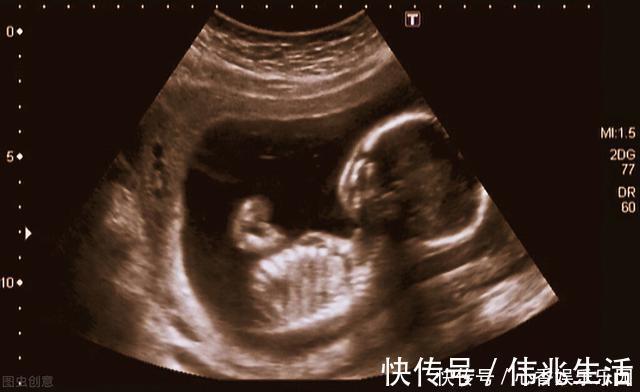

但是在做B超时,他们看到了胎儿,他已有成形的手指和脚趾,正在吮吸着自己的手指头,那个样子看起来很幸福。这“幸福的胎儿”让父亲心痛,虽然还在妈妈的肚子里,可是他们非常爱他。他们决定要救这个孩子。于是两人走遍全国,四处求医,最后他们选择了一种处于实验阶段的手术,叫宫内手术,就是在动态实时超声的引导下,给胎儿做手术。这种手术的危险不言而喻,但是克鲁斯·兰德夫妇仍然选择了它!

克鲁斯·兰德太太是第八个接受这种手术的孕妇,在她之前的七名孕妇中,手术成功的只有四个人,但他们无论如何都要试一试。这次手术是成功的,医生在实时超声的引导下,迅速而又准确地去除了胎儿肺部的压迫。很多年后克鲁斯·兰德太太仍然能够清晰地回忆起当时的情景:手术结束时,医生和护士们情不自禁互相击掌庆贺,她兴奋得痛哭流涕,同时又感到幸福无比,因为孩子得救了!手术后的几个月,胎儿出生了。在他出生的一瞬间,洪亮地哭出了第一声,这说明他的肺已经正常了。